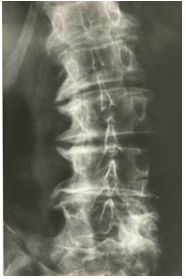

8. 48歲肥胖女性走路時腰部會酸痛,蹲下去及站起來有困難,腰椎X-光檢查有異常發現如圖。請問下列的何種治療最為有效? (A) NSAIDs (B) Oral glucosamine (C) Intra-articular steroid injection (D) Physical therapy (E) Reduction of body weight